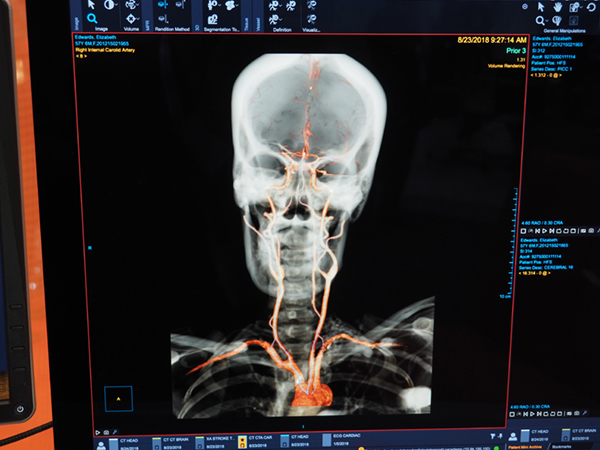

AIで頭部・血管をあらかじめ認識して血管の抽出を高速化(W.I.P.)